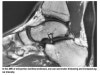

MRI : 아킬레스건염(Achilles tendinitis, Achilles tendonitis)